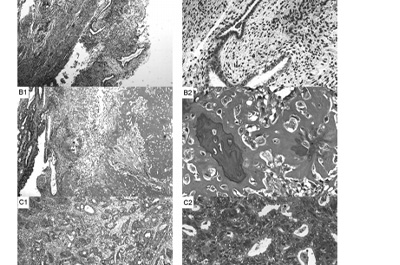

这项研究报告了1例59岁绝经后女性患子宫骨肉瘤并表现为恶性混合苗勒管肿瘤的罕见病例。通过MRI、超声检查、血清肿瘤标志物检测、手术及病理诊断等方式,对患者病情进行详细分析,并探讨了该疾病的相关特征和治疗方案。

结果发现,患者经手术和病理诊断,确诊为子宫骨肉瘤合并恶性混合苗勒管肿瘤,包含子宫内膜腺癌、软组织肉瘤和骨肉瘤成分,且存在淋巴结转移,分期为IIIC2期。

该疾病临床症状不典型,易被误诊为子宫肌瘤,影像学检查难以确诊肿瘤性质。经手术切除及紫杉醇联合卡铂化疗后,患者目前无复发或转移,生活质量良好,但该疾病总体预后较差,5年总生存率仅16.3%。